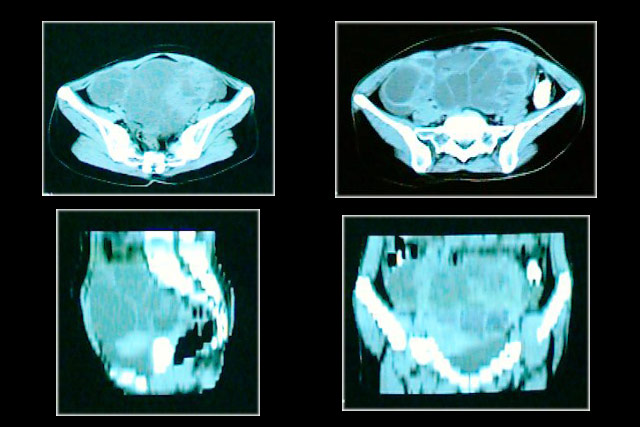

Vemos nos cortes tomográficos imagem tumoral,

com debris, localizada na pelves.